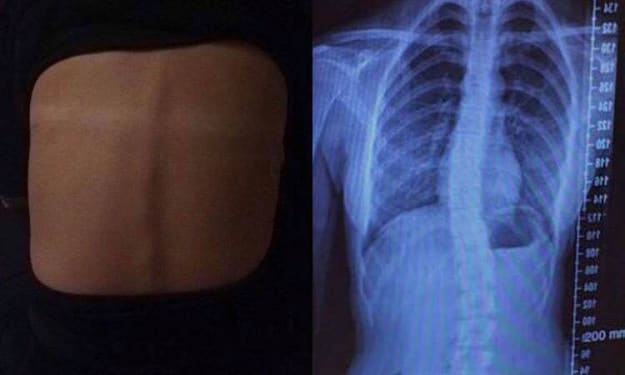

Faith for an S-Shaped Back

It's crazy to think how quickly something can change your life forever. The slightest thing can cause a huge impact… From either just carrying a heavy bag to doing sit-ups or walking with the wrong "technique." I never even thought about the implications of carrying a side bag instead of a backpack with all my books in (ones I sometimes didn’t even need for the day) in my bag for school EVERY DAY!

By Imogen Szecowka8 years ago in Longevity